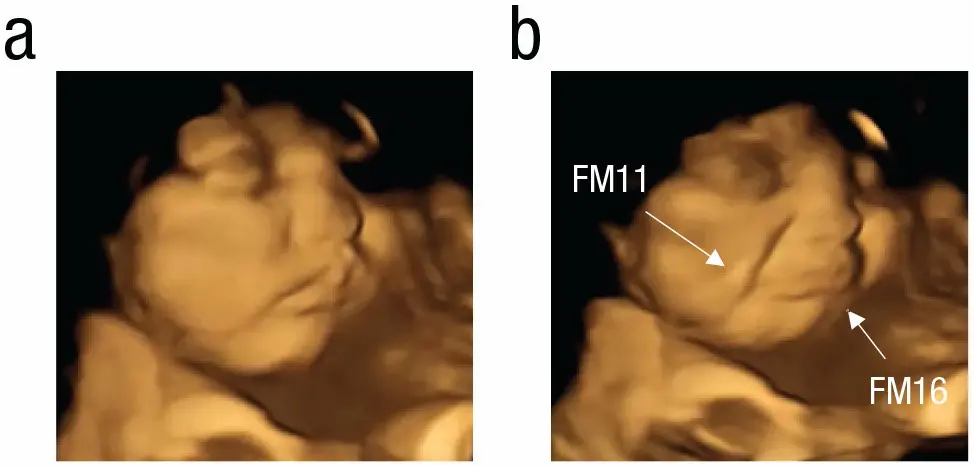

Les images obtenues ont permis aux chercheurs d'observer la façon dont les futurs bébés réagissaient lorsque leur mère mangeait de la carotte ou du chou kale. Les fœtus exposés à la carotte ont montré "un visage riant" (voir image 1), tandis que ceux dont les mères mangeaient du chou kale présentaient "un visage grimaçant" (voir image 2), ont établi les chercheurs.